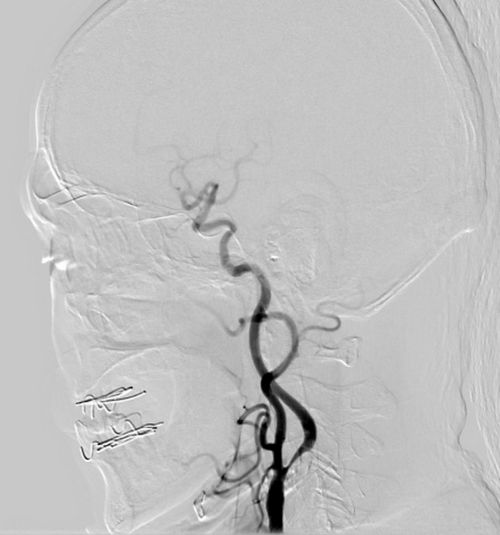

患者CABG术后,患者近2各月来间断出现头晕,神经系统查体未见阳性体征,左侧颈动脉听诊区可闻及杂音, 查颈动脉B超:左侧颈总动脉分叉处狭窄72%。后行全脑血管造影,显示左颈内动脉重度狭窄90%,左椎动脉开口处重度狭窄90%,右侧颈动脉分叉处重度狭窄70%,右椎开口狭窄60%。

患者5年前因脑梗死曾于安贞医院治疗,当时发现右侧颈动脉狭窄,于天坛医院行右侧颈动脉支架植入术。一周前门诊复查血管超声,发现左侧颈总动脉狭窄,为进一步诊治收入院。全脑血管造影示右侧颈动脉支架血流通畅,右颈外动脉闭塞,左颈内动脉重度狭窄。